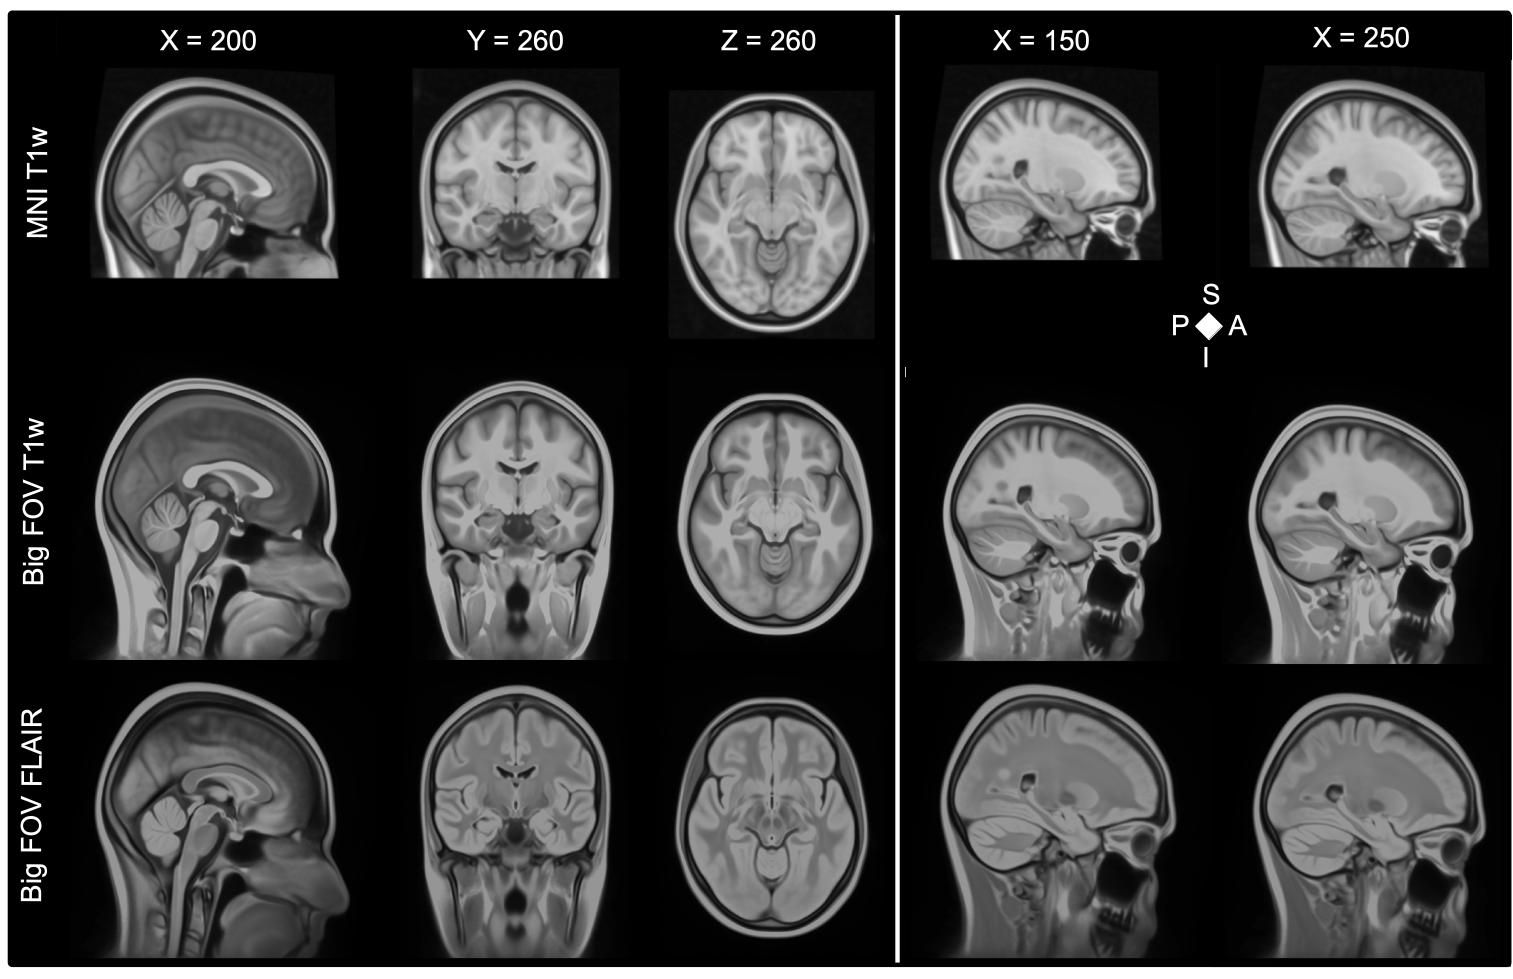

Blurriness in big FOV template

However, we found that the occipital GM regions look blurry on our template (see attached figure). Is there something you could suggest to avoid this?

So I'm guessing that you're registering a bunch of images to the MNI template and averaging the result. If so, it's a perfectly reasonable approach but this would not be considered an "ANTs template." Although you're capturing the intensity variation in your population, the shape variation is completely ignored (as well as the intensity sharpening which does help with some blurriness). For your specific issue of blurriness, I would look at each individual image warped to the MNI template space and see how well each image is aligned in occipital region.